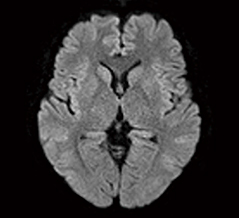

症例2:頭部拡散強調画像(syngo RESOLVE)

「ルーチン検査では,体動補正のアプリケーションである“syngo BLADE”を使用していますが,アーチファクトのない精度の高い画像を撮像できています。また,顔面けいれんや動眼神経麻痺の検査には,高速撮像法である“syngo SPACE”を用いており,脳神経を高精細に描出しています。さらに,拡散強調画像のアプリケーションである“syngo RESOLVE”もとても高く評価しています。拡散強調画像はMAGNETOM Amiraの本稼働前から期待していたのですが,syngo RESOLVEでは歪みのない,アーチファクトを抑えた画像が得られており,後頭蓋窩の梗塞診断において非常に有用です」